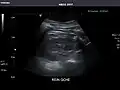

Spleen -

Spleen: Normal in size.